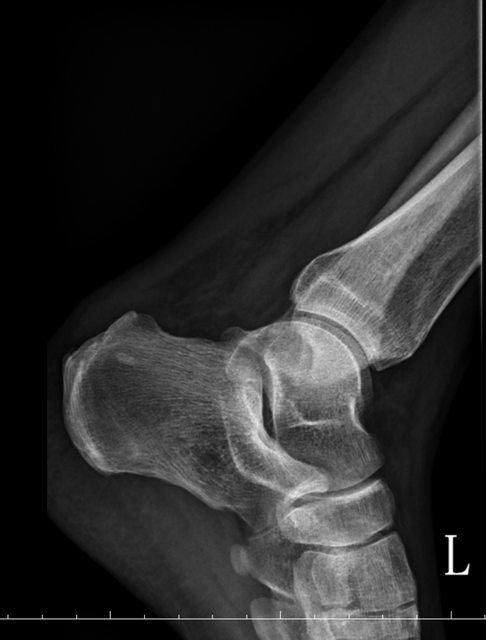

https://i.imgur.com/9HfkOHc.png

骨盆 https://i.imgur.com/h7KknkX.png

股骨頭放大特寫...左邊是右股骨 你覺得哪邊比較正常? https://i.imgur.com/16erxqZ.png

https://i.imgur.com/7NtJDKg.png

https://i.imgur.com/R4JFreK.jpg

醫生似乎很急 就問了二個問題就叫我去照X光 可能就一分鐘吧 回來看了下X光就說可能有神經壓迫 又是14天的消炎止痛藥 說還會痛再來回診或去看脊柱專科或復健科 感覺就是浪費了一天的時間排隊再排隊 沒得到答案 也沒有得到解決... 然後拿了吃越多可能洗腎越快的止痛藥 會不會下次脊柱專科也開14天消炎止痛說如果還有問題叫你去掛神經科? 為何不給我照MRI呢?我第一次去看問了MRI就還是只給我照X光 1.2期X光照了也不一定有異常,我實在不懂不用MRI的邏輯 體驗實在太差了,當然我也知道當有一百號排隊時問診就不可能細到哪怕只有15分 我想不等直接掛看看禮拜三神經科會怎解釋了 ※ 編輯: capybaradash (118.166.44.25 臺灣), 07/31/2023 14:29:17 ※ 編輯: capybaradash (118.166.44.25 臺灣), 07/31/2023 14:37:27